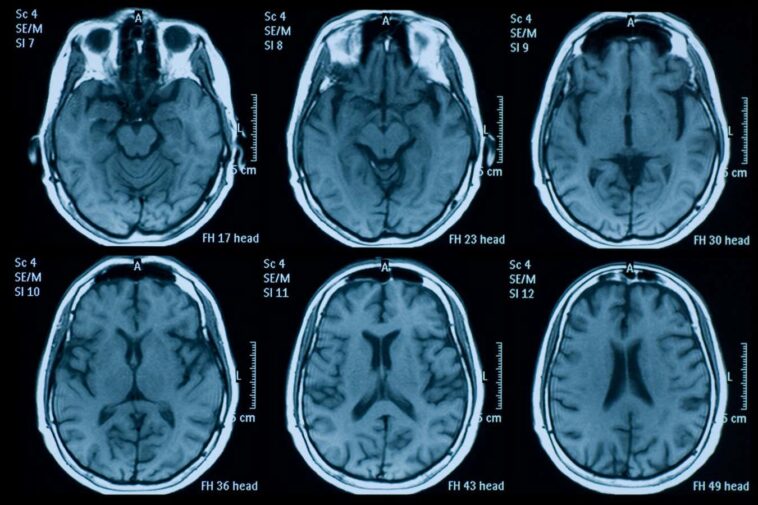

Pour comprendre cela, Ali-Reza Mohammadi-Nejad à l'Université de Nottingham, au Royaume-Uni, et ses collègues ont formé un modèle d'apprentissage automatique sur 15 000 scans cérébraux pour identifier comment sa structure change avec l'âge.

Ils ont ensuite nourri les paires de modèles de scanneurs cérébrales de 996 volontaires de l'étude UK Biobank. Parmi ceux-ci, 564 ont fait des deux scans avant mars 2020, lorsque Lockdown a été introduit au Royaume-Uni et a agi en tant que groupe témoin. Les 432 bénévoles restants ont eu un scan avant mars 2020 et un plus tard. Chaque scan était séparé de trois ans, en moyenne, avec un écart minimum de deux ans.

Lorsque les chercheurs ont comparé des individus des deux groupes – qui ont été appariés pour l'âge, le sexe et la santé globale – ils ont constaté que la pandémie peut avoir accéléré le vieillissement de notre cerveau de 5,5 mois, sur la base de changements structurels en matière blanche et grise. Cela était vrai même parmi ceux sans infection connue de Covid-19, qui a été enregistré dans le cadre du projet biobanque.